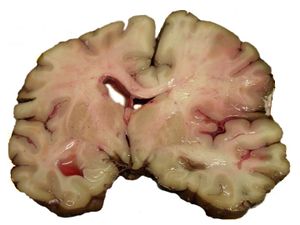

السكتة الدماغية

A slice of brain from the autopsy of a person who suffered an acute middle cerebral artery (MCA) stroke